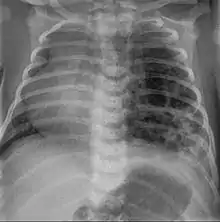

Three quarters of affected patients are asymptomatic. However, 25% develop cyanosis, pneumothorax, and show signs of increased breathing difficulty (tachypnoea and intercostal retractions).At examination, they may show hyper-resonance at percussion, diminished vesicular murmur and an asymmetrical thorax.

CPAMs are often identified during routine prenatal ultrasonography. Identifying characteristics on the sonogram include: an echogenic (bright) mass appearing in the chest of the fetus, displacement of the heart from its normal position, a flat or everted (pushed downward) diaphragm, or the absence of visible lung tissue.

CPAMs are classified into three different types based largely on their gross appearance. Type I has a large (>2 cm) multiloculated cysts. Type II has smaller uniform cysts. Type III is not grossly cystic, referred to as the "adenomatoid" type. Microscopically, the lesions are not true cysts, but communicate with the surrounding parenchyma. Some lesions have an abnormal connection to a blood vessel from an aorta and are referred to as "hybrid lesions."

Imaging

The earliest point at which a CPAM can be detected is by prenatal ultrasound. The classic description is of an echogenic lung mass that gradually disappears over subsequent ultrasounds. The disappearance is due to the malformation becoming filled with fluid over the course of the gestation, allowing the ultrasound waves to penetrate it more easily and rendering it invisible on sonographic imaging. When a CPAM is rapidly growing, either solid or with a dominant cyst, they have a higher incidence of developing venous outflow obstruction, cardiac failure and ultimately hydrops fetalis. If hydrops is not present, the fetus has a 95% chance of survival. When hydrops is present, risk of fetal demise is much greater without in utero surgery to correct the pathophysiology. The greatest period of growth is during the end of the second trimester, between 20–26 weeks.